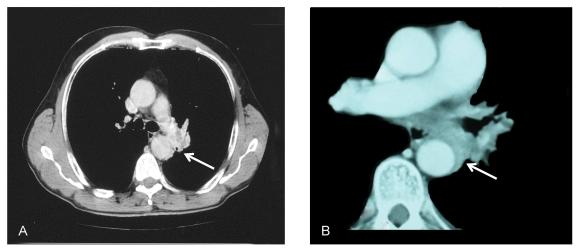

Thirteen patients with locally advanced (T4) NSCLC and invasion of the descending aorta underwent pneumonectomy (n=9) or lobectomy (n=4) together with aorta en bloc resection and reconstruction (n=8) or subadventitial dissection (n=5), complete lymph node dissection, and had microscopic unsuspected node metastasis at N1 (n=5) and N2/3 (n=8) levels of whom 12 received radiation therapy. Clamp-and-sew was used to resect and reconstruct the aorta.

Operative mortality and morbidity rate was 0% and 23%, respectively. Four patients died of systemic tumor relapse and 2 of local recurrence. Six patients were alive after a median follow-up of 40 months (range 15-125 months). Overall 5-year survival rate was 45%. Median survival time and 5-year survival rate of patients after aortic resection was 35 months and 67%, respectively, and was 17 months and 0%, respectively, after aortic subadventi-tial dissection (p=0.001). N1 and N2 nodal status adversely affected survival, but survival difference was not significant (N1 versus N2/3; 52% versus 39% at 5 years; p=0.998).

Aortic resection with single station node positive T4 lung cancer can achieve long-term survival. The data indicate that aortic resection-reconstruction is associated with better outcome than subadventitial dissection.